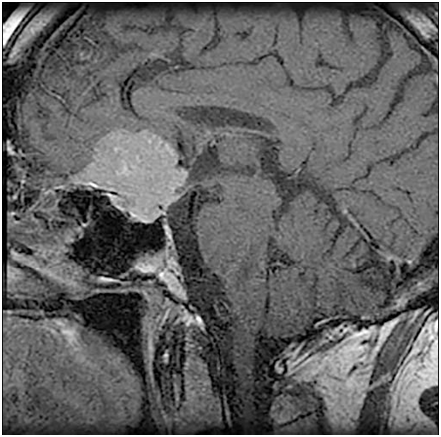

A 56-year-old man was referred urgently by an ophthalmologist after presenting with a 6-month history of deteriorating vision. The patient had a 40 pack-year smoking history. Before his vision problem, he had never visited his general practitioner.

Investigations:

-serum cortisol (09.00 h)389 nmol/L (200–700) serum testosterone8.6 nmol/L (9.0–35.0)

-plasma follicle-stimulating hormone2.1 U/L (1.0–7.0) plasma luteinising hormone2.4 U/L (1.0–10.0)

-serum prolactin896 mU/L (<360)

-serum thyroid-stimulating hormone1.4 mU/L (0.4–5.0) MR scan of pituitarysee image

What is the most likely diagnosis?

1. craniopharyngioma

2. meningioma

3. non-functioning adenoma

4. prolactinoma

5. Rathke’s cyst

Answer(s): B